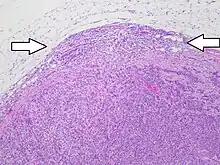

Lymph node metastasis is the spread (metastasis) of cancer cells into a lymph node.

Generally, metastases form first in the lymph nodes that are closest to the primary tumor. This is because the lymphatic fluid (lymph) of the cancerous organ or tissue flows first to these nearby lymph nodes. The tumor cells reach the lymph nodes via this lymphatic pathway, where they remain and proliferate. These spreading cancer cells grow in the lymph nodes, which causes the affected lymph nodes to get bigger.